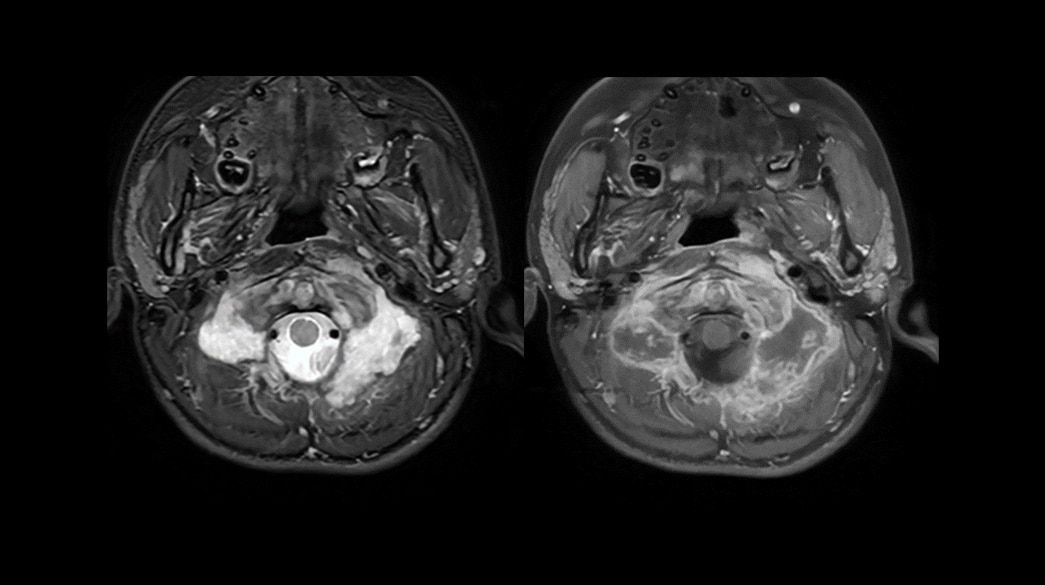

Consistent

Motion and distortion-reduced scans with high-resolution and contrast